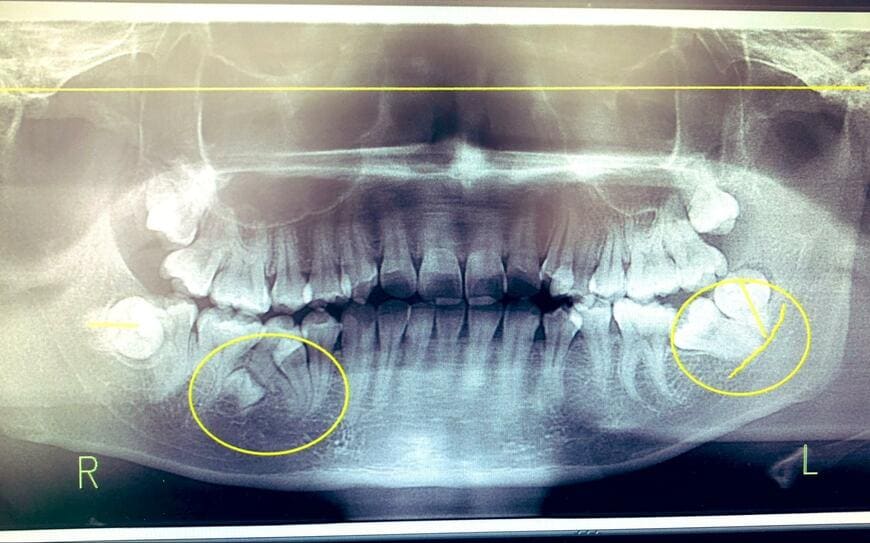

「歯が人より6本多かったので、抜いたらその後で追加で2本生えた 」そんなコメントとともに投稿された1枚の写真。

そこに写っていたのは、投稿主さんの歯を撮影したレントゲン写真でした。

レントゲン写真をよく見ると、歯と歯の間に小さな歯がいくつか埋まっています。

投稿主さんは、20歳頃から前歯の間に別の歯が生えてきたことをきっかけに歯科医院を受診し、そこで「歯が人より6本多い」ことを知ったそうです。